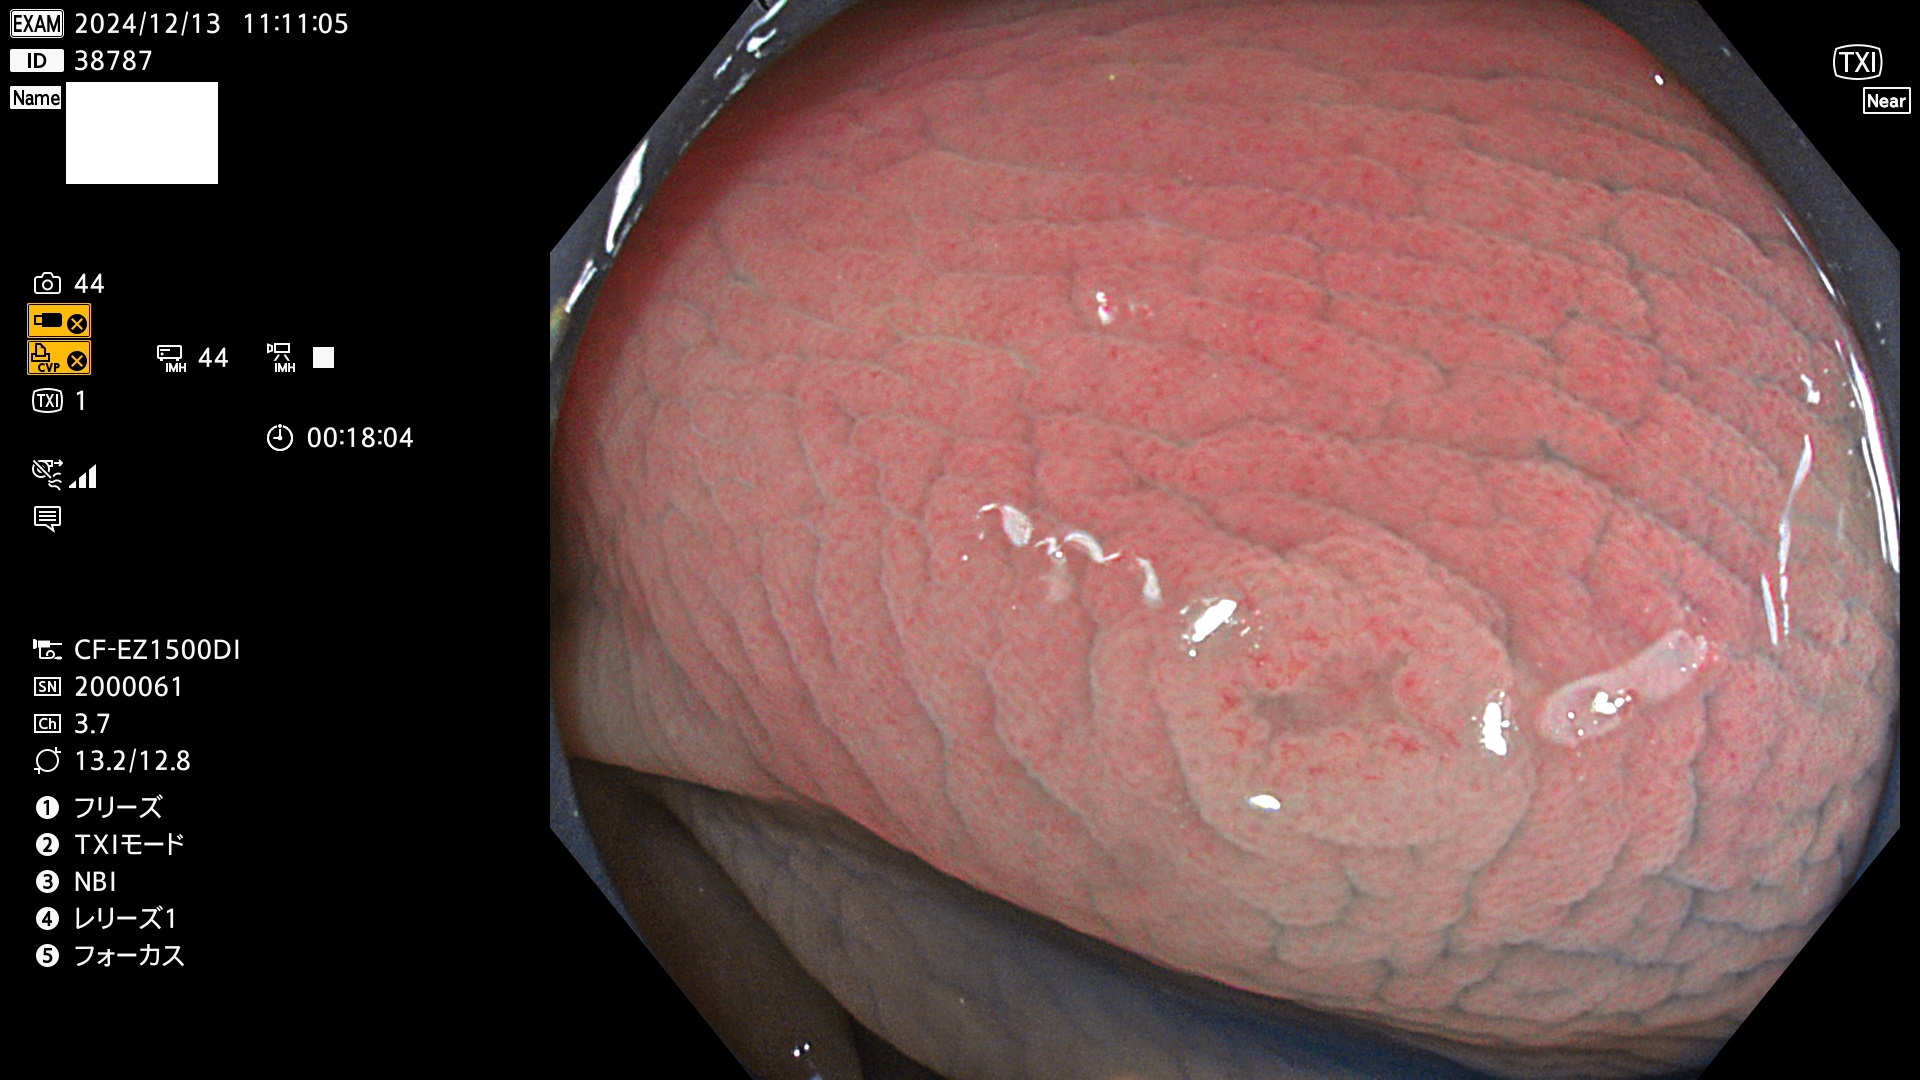

完全に平坦な物をUb、陥凹している物をUcと呼びます。最も発見が難しく危険な病変です。

専門的)何故、陥凹していると危険? 癌遺伝子の変異が蓄積すると細胞分裂が盛んになり隆起するのでは?と通常は思われるでしょう。しかし実際は逆です。これは2022年の記事にある「細胞はストレスに直面したら細胞分裂を止める(細胞老化に入り休眠する)という生命の基本的現象」によるものです(Oncogene Stress)。細胞老化を起こすのが癌抑制遺伝子で、この安全装置(ブレーキ)が壊れると癌になります(休眠からの覚醒)。ですから陥凹は「まだ癌では無いが癌化の直前」を意味します。特に「小サイズなのに陥凹している」病変は短期間に腫瘍進化(IntraTumor Heterogenity⇒2021年記事)が起きたことを意味します(=ゲノム不安定性

毎週の検査(木・金・土・日)に発見されたUb、Uc型・腺腫を、その週の日曜の夜にUPし1週間、提示します。

抽出の対象期間 2024年12月12日〜12月16日の5日間(60件の検査)13件 (13/60=21%)